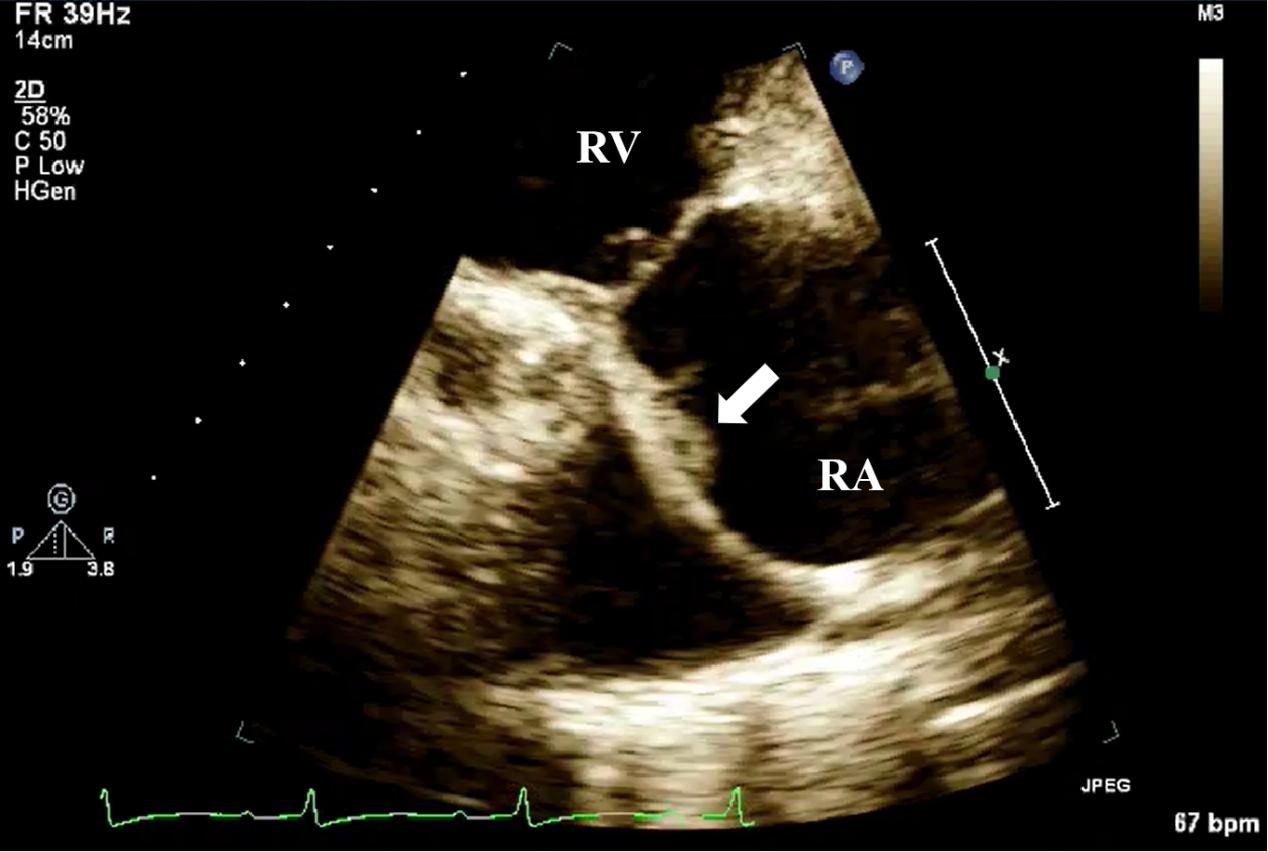

Echocardiography plays a critical role in the diagnosis of CIED-IE. Studies show that approximately 50% of CIED-IE patients exhibit echocardiographic evidence of valvular vegetations, most commonly on the tricuspid valve (Fig. 8) [51]. TEE is superior to TTE in the diagnostic evaluation of CIED-IE. Tricuspid valves or lead vegetations can be detected in 61% of cases with TEE, but in only 57% with TTE . In addition to the identification of vegetations, TEE can also visualize the leads within the proximal superior vena cava, a region that is often obscured by TTE. In patients with persistently positive blood culture but negative TTE and TEE findings, intracardiac echocardiography (ICE) may be considered for further diagnosis. ICE is widely utilized in the diagnosis of CIED-IE and can more effectively delineate the intracardiac structures. Studies have shown that ICE is more sensitive than TEE in detecting smaller or atypically located lesions [52]. Narducci et al. [53] conducted a comparative study of TEE and ICE in 162 CIED-IE patients, and found that the diagnosis of ICE was significantly higher than that of TEE. ICE can be a substitute for TEE especially in patients with esophageal cancer or those in whom cardiac structures need to be evaluated prior to lead extraction. Although ICE has high spatial and temporal resolution, its main limitation lies in its invasiveness. Due to the risk of complications, it is recommended to give priority to ICE in patients with who already have established vascular access [54].

Fig. 8. TTE detection of CIED-IE valve vegetation. TTE shows moderately echogenic vegetation (white arrow) attached to the pacemaker lead in the right ventricular inflow tract view. CIED-IE, cardiac implantable electronic device-related infective endocarditis; TTE, transthoracic echocardiography; RV, right ventricle.